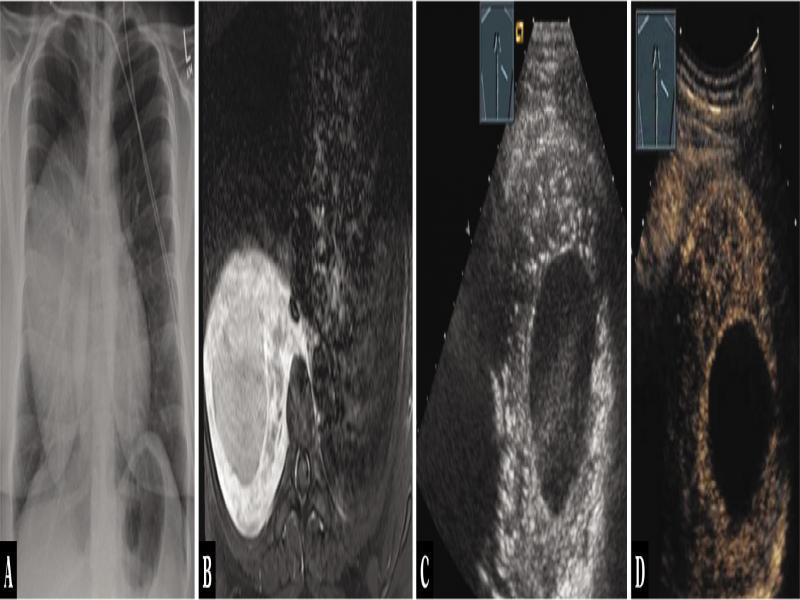

Fig. 16.

A 27-year-old male patient with thoracic pressure sensation and a mediastinal tumor in the posterior mediastinum on chest x-ray (A). The tumor was visualized by MRI (T2 weighting) (B). Thoracic ultrasound indicated an inhomogeneous hypoechoic tumor, marginally solid with small reflexogenic lesions, centrally anechoic (C), which on contrast-enhanced ultrasound showed mixed centrally absent enhancement and peripheral hypoenhancement (D). Ultrasound-guided biopsy was performed, and the diagnosis of ganglioneuroma was histologically confirmed